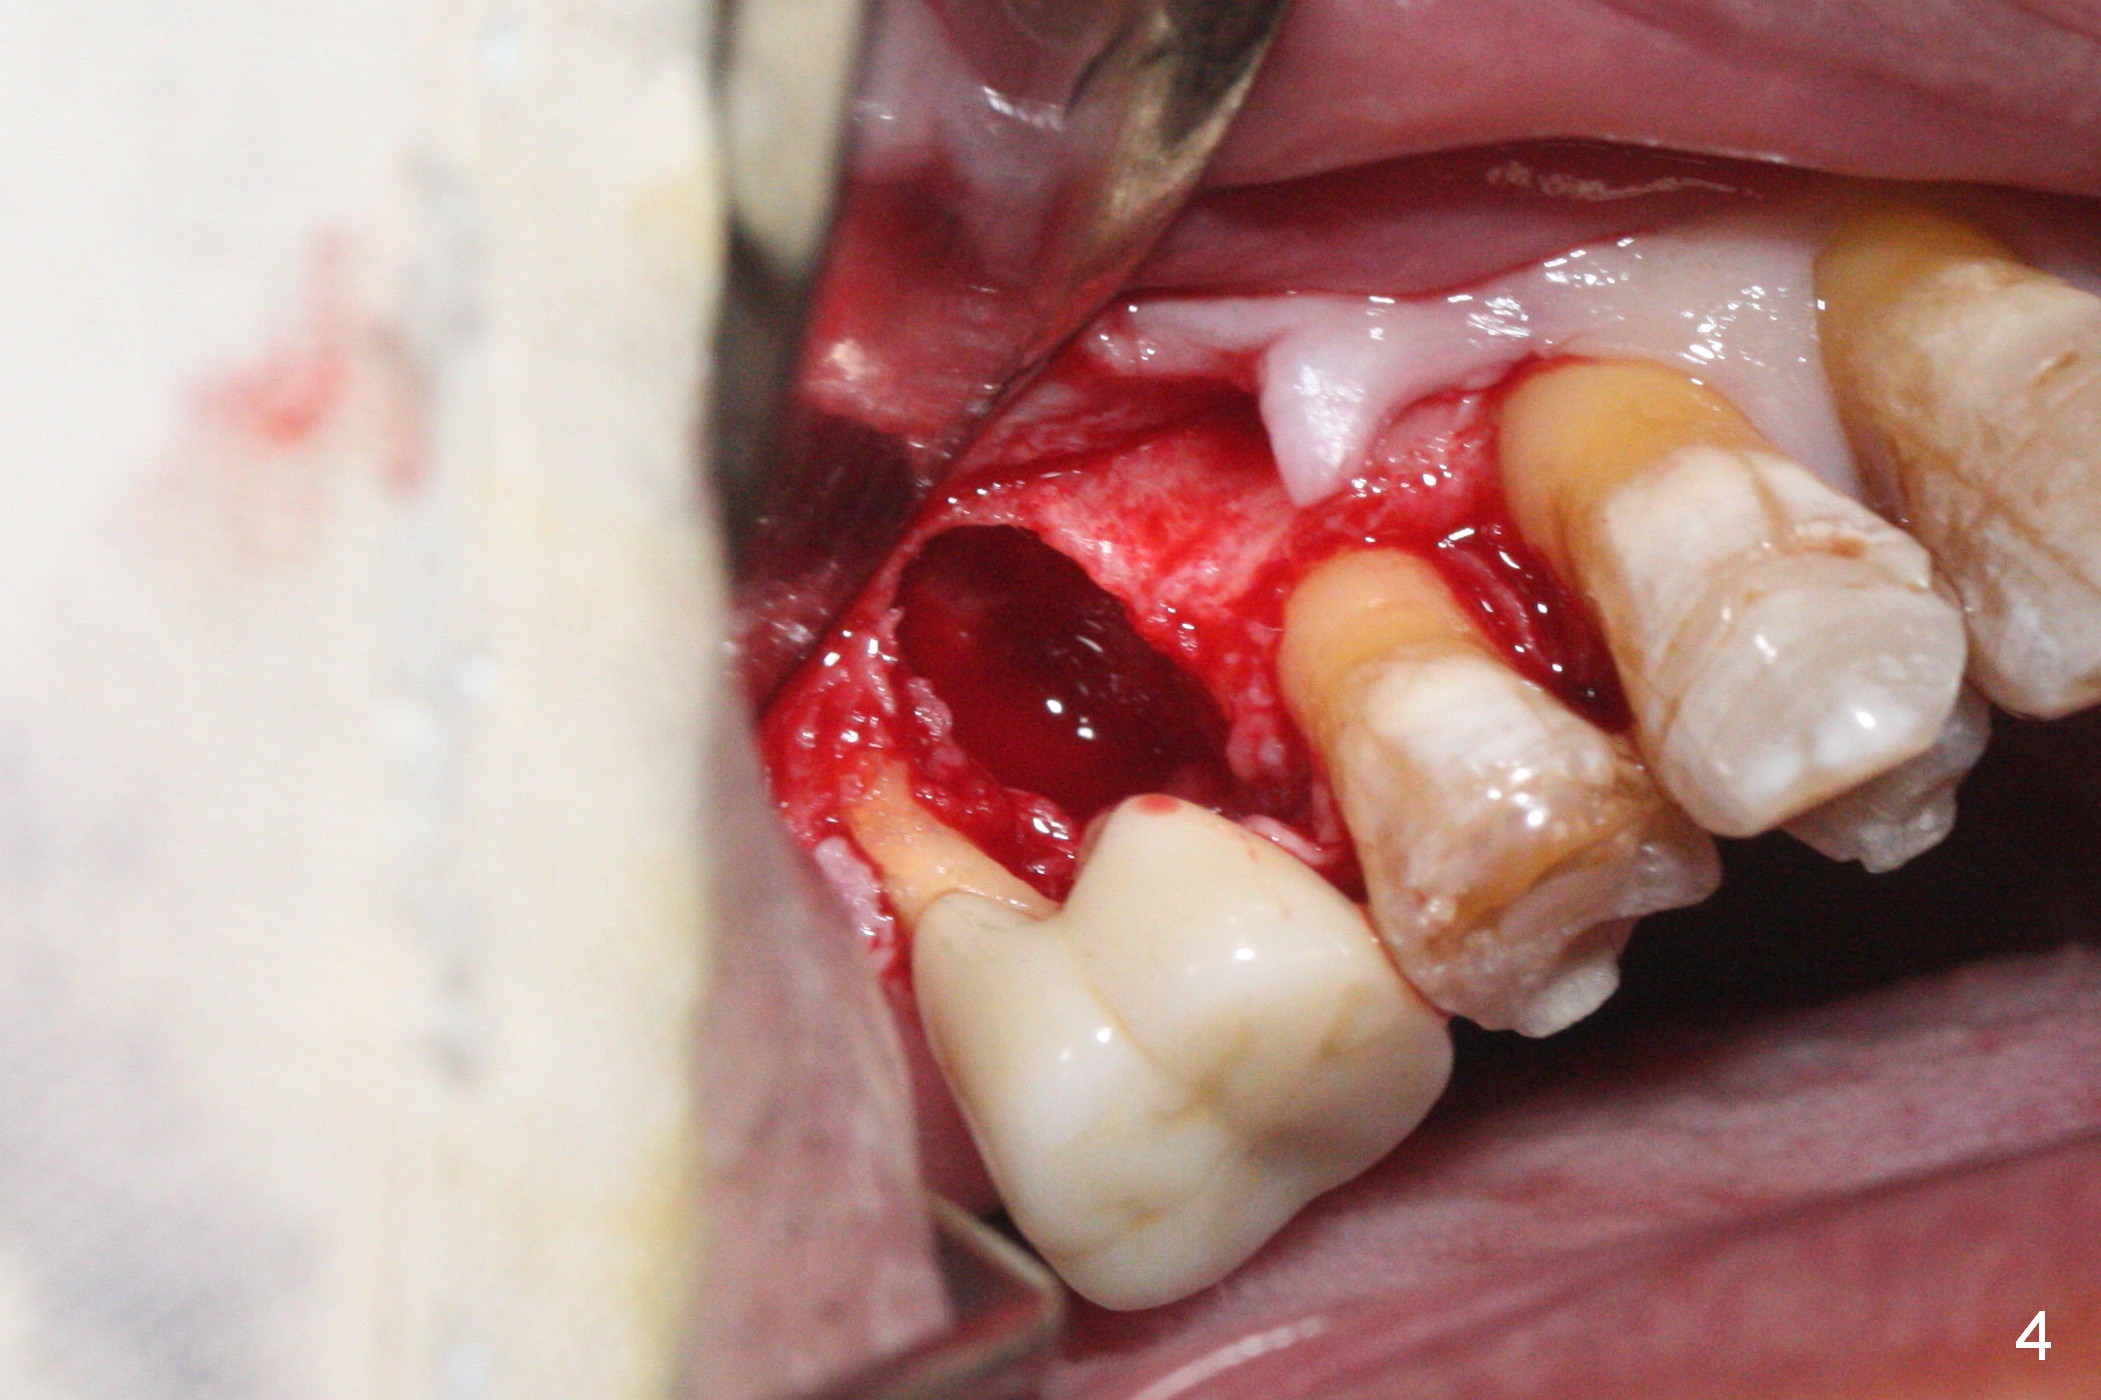

A 56-year-old man has discomfort associated with the tooth #3 one year and a half after root canal therapy (Fig.1: mesiobuccal root vertical fracture). Since an implant is just placed at #19 and another one will be encouraged to be placed at #2 (Fig.2), root amputation may be a valid treatment modality (Fig.3,4). After debridement and Clindamycin topical application, allograft/Osteogen is placed (Fig.5,6 (dashed line)), followed by Osteogen plug (Fig.7 *). Discomfort apparently shifts to the distobuccal root 9 months postop, while the MB defect seems to heal (Fig.8 *). Extraction and implant is expected.